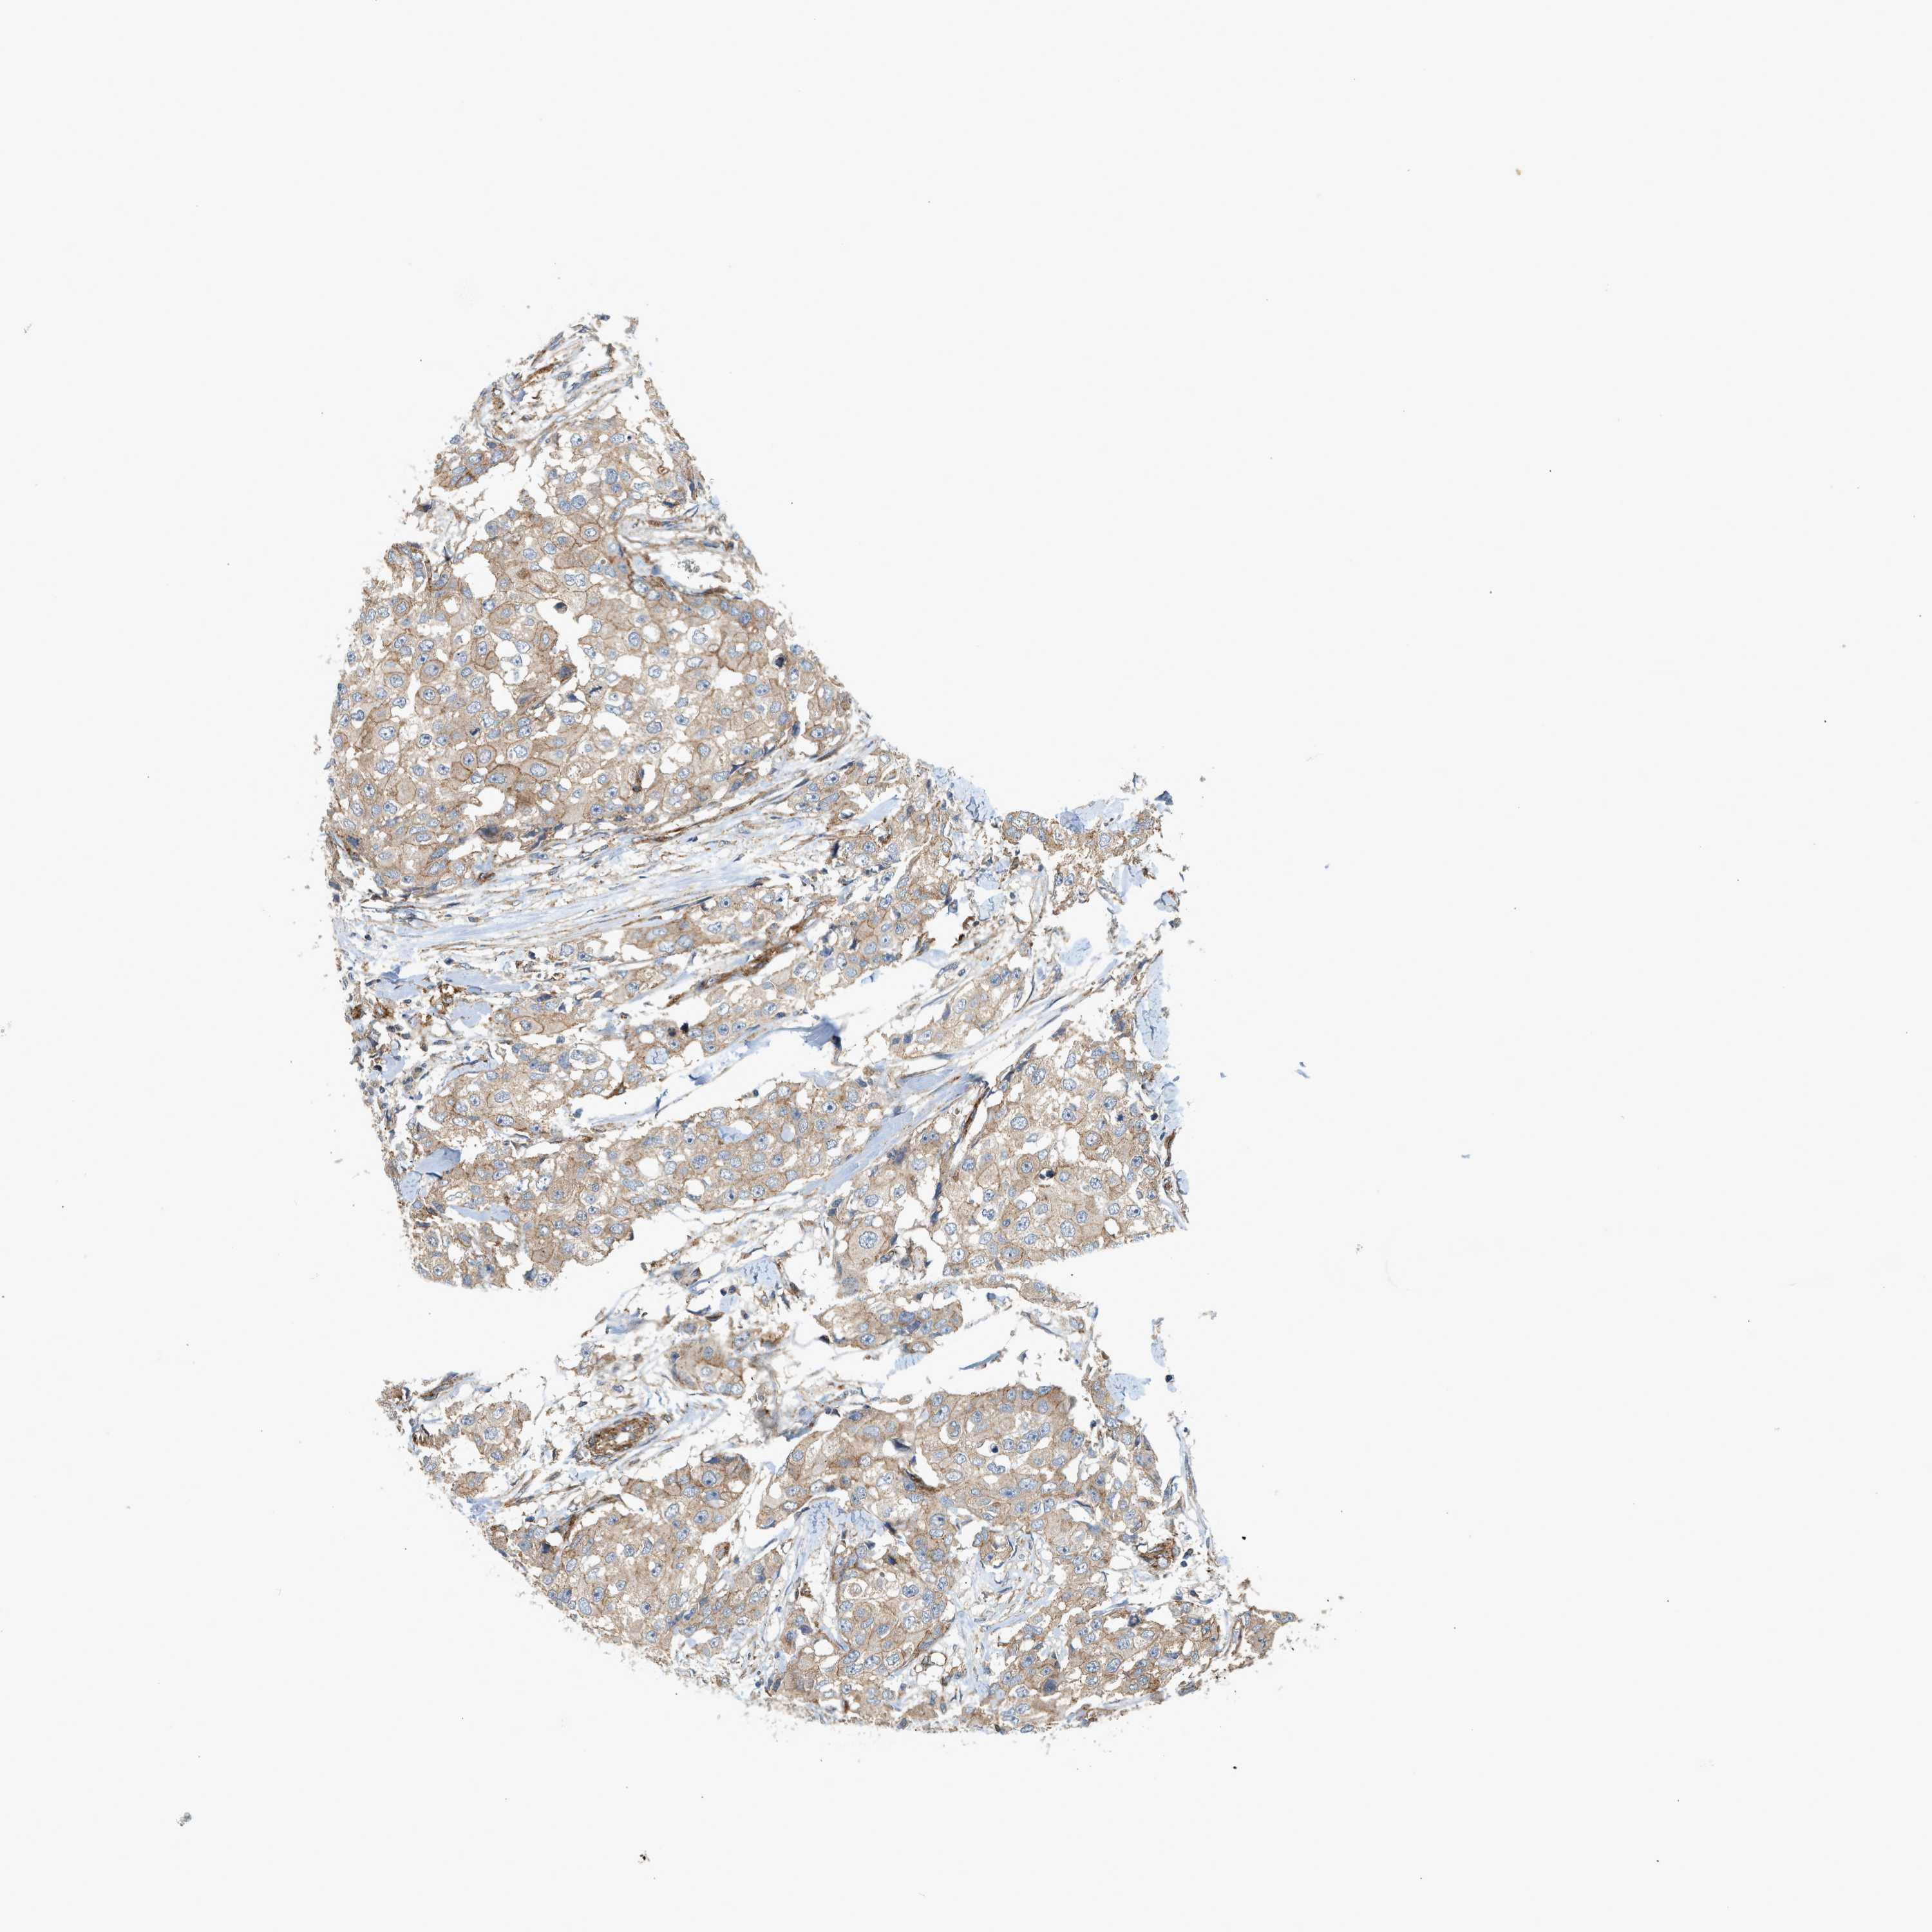

CANCER BREAST CANCER Show tissue menu

BRCA TCGA BRCA VALIDATION PROTEIN EXPRESSION